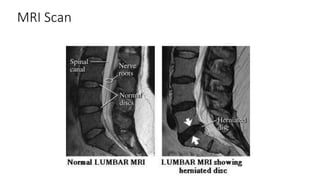

MRI Scan

Imaging of the Herniated Disc